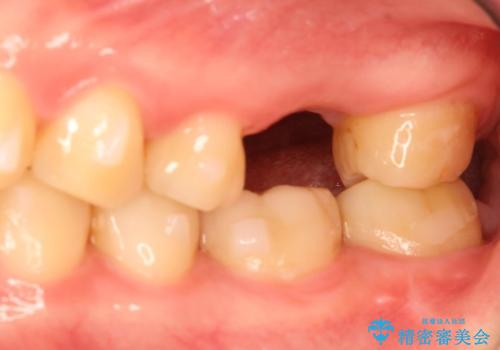

奥歯が割れてしまった! → インプラントによるかみ合わせの回復

- 歯根破折を生じた奥歯を抜歯後、治癒の期間を経てインプラントを埋入